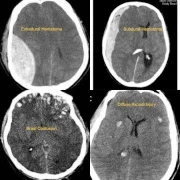

We specialize in neuro-trauma emergency care in Thane, providing immediate surgical interventions for patients suffering from severe head injuries, traumatic brain hemorrhages, skull fractures, and spinal cord injuries. Our dedicated neurotrauma emergency unit in Thane is equipped with 24×7 neurosurgical support, advanced ICU care, and rapid imaging facilities, ensuring that critical patients receive the fastest and most effective treatment possible.

Educational Resources: Case studies and educational blogs about ailments including listhesis and cerebral hematomas.

– Traumatic Brain Injury